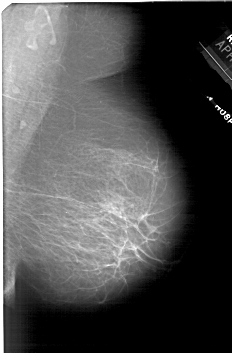

A_1865_1.LEFT_CC

LEFT_CC LINES 6826 PIXELS_PER_LINE 3841 BITS_PER_PIXEL 12 RESOLUTION 43.5 OVERLAY